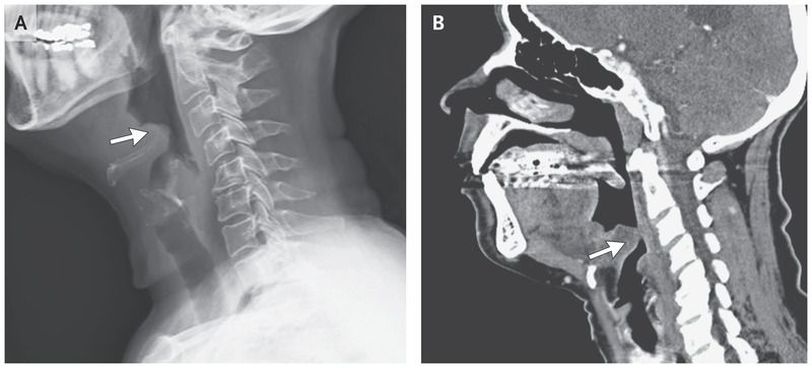

A previously healthy 65-year-old woman presented to the emergency department with a 7-day history of throat pain, difficulty swallowing, muffled voice, and subjective fevers. On presentation, she was afebrile and hemodynamically stable with normal oxygen saturation (blood pressure, 140/86 mm Hg; oxygen saturation, 98% while the patient was breathing ambient air). Physical examination revealed mild tenderness and swelling in the anterior neck, without cervical lymphadenopathy or drooling. Lateral soft-tissue radiography of the neck showed the “thumb sign” (Panel A, arrow), indicating a swollen epiglottis, suggestive of epiglottitis. Computed tomography of the neck revealed substantial swelling and edema of the epiglottis (Panel B, arrow), the base of the tongue, and the lingual tonsil. Indirect laryngoscopy revealed erythema and inflammation of the epiglottis and the base of the tongue, with clinically significant hypertrophy of the lingual tonsil and phlegm in the throat. Ceftriaxone and dexamethasone were initiated, owing to the risk of airway compromise. The patient was monitored closely in the hospital for 48 hours. Blood cultures remained negative. The patient’s symptoms improved, and within 3 days after presentation, she was able to consume an oral diet. She was discharged home to complete 1 additional week of antimicrobial treatment with oral cefuroxime.